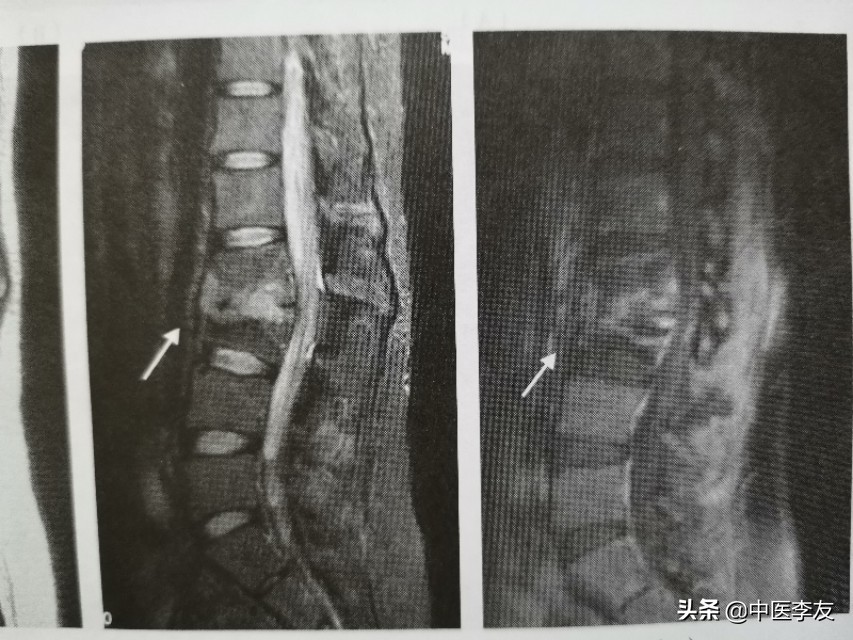

3.MRI,表现是显示脊椎结核病灶和范围最敏感的方法,可发现椎体内早期炎性水肿。病灶T1WI表现为低信号,T2WI多表现为混杂高信号;GD-DTPA增强不均匀强化。脓肿和肉芽肿在T1WI上呈低信号,T2WI多为混杂高信号,部分均匀高信号,增强检查肉芽肿不均匀,均匀强化,脓肿壁薄且均匀的环状强化。

腰椎结核